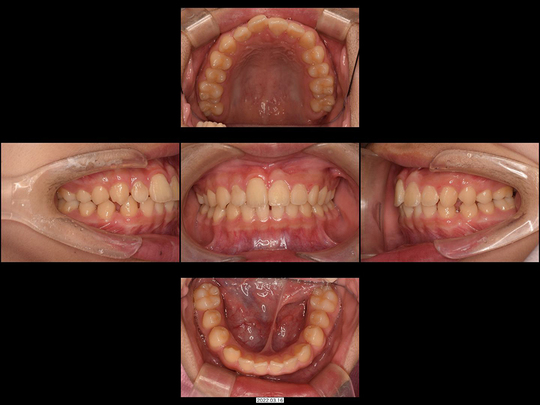

Yさん 9歳 男性

矯正前

矯正治療中

矯正後

治療の説明

前歯が生えてこないことをご不安に思われていたものの、「様子見しましょう」と言われ続けたとのことです。

CT検査の結果、埋伏している前歯に「過剰歯(かじょうし)」とよばれる余分な歯があり、本来の歯に引っかかっている状況でした。過剰歯を抜歯した後、事前に準備したお口の中に装着済みのワイヤー矯正装置で牽引を開始。奥歯の乳歯から永久歯の生え変わりのスペースもないので、併せてあごの骨も拡大しました。

治療の期間・回数

36か月、36回

​費用

618,000円

リスクや副作用:出血を伴う可能性があります。治療後に、痛みや腫れ、出血を引き起こす可能性があります。

装置に慣れるまでに1週間ほどかかる可能性があります。歯列を広げる過程で少し痛みを感じる可能性があります。装着時に多少しゃべりづらくなる可能性があります(2~3週間ほどで慣れます)。